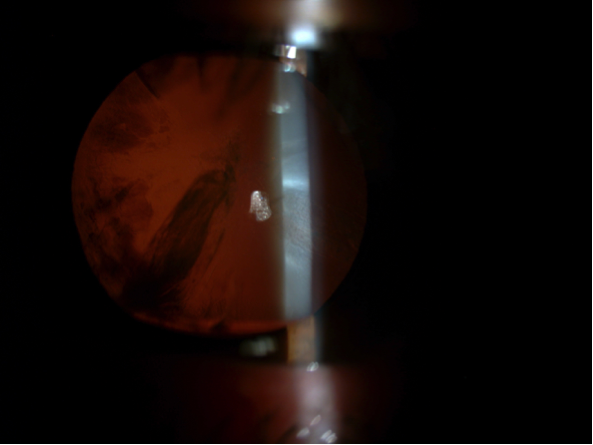

Alguna de las circunstancias que pueden hacer la cirugía más laboriosa es la insuficiente dilatación de la pupila o el cierre de la misma durante la intervención, más frecuente en pacientes que toman tratamientos para la hiperplasia benigna de próstata, que con frecuencia afectan al iris, causando lo que se denomina Sindrome de Iris Flacido. En el siguiente video, podemos ver el ejemplo del segundo ojo de un caso así, donde directamente, por la experiencia vivida en el otro ojo, dilatamos la pupila mecánicamente con retractores de iris en previsión de posibles complicaciones, completando la cirugía sin incidencias.